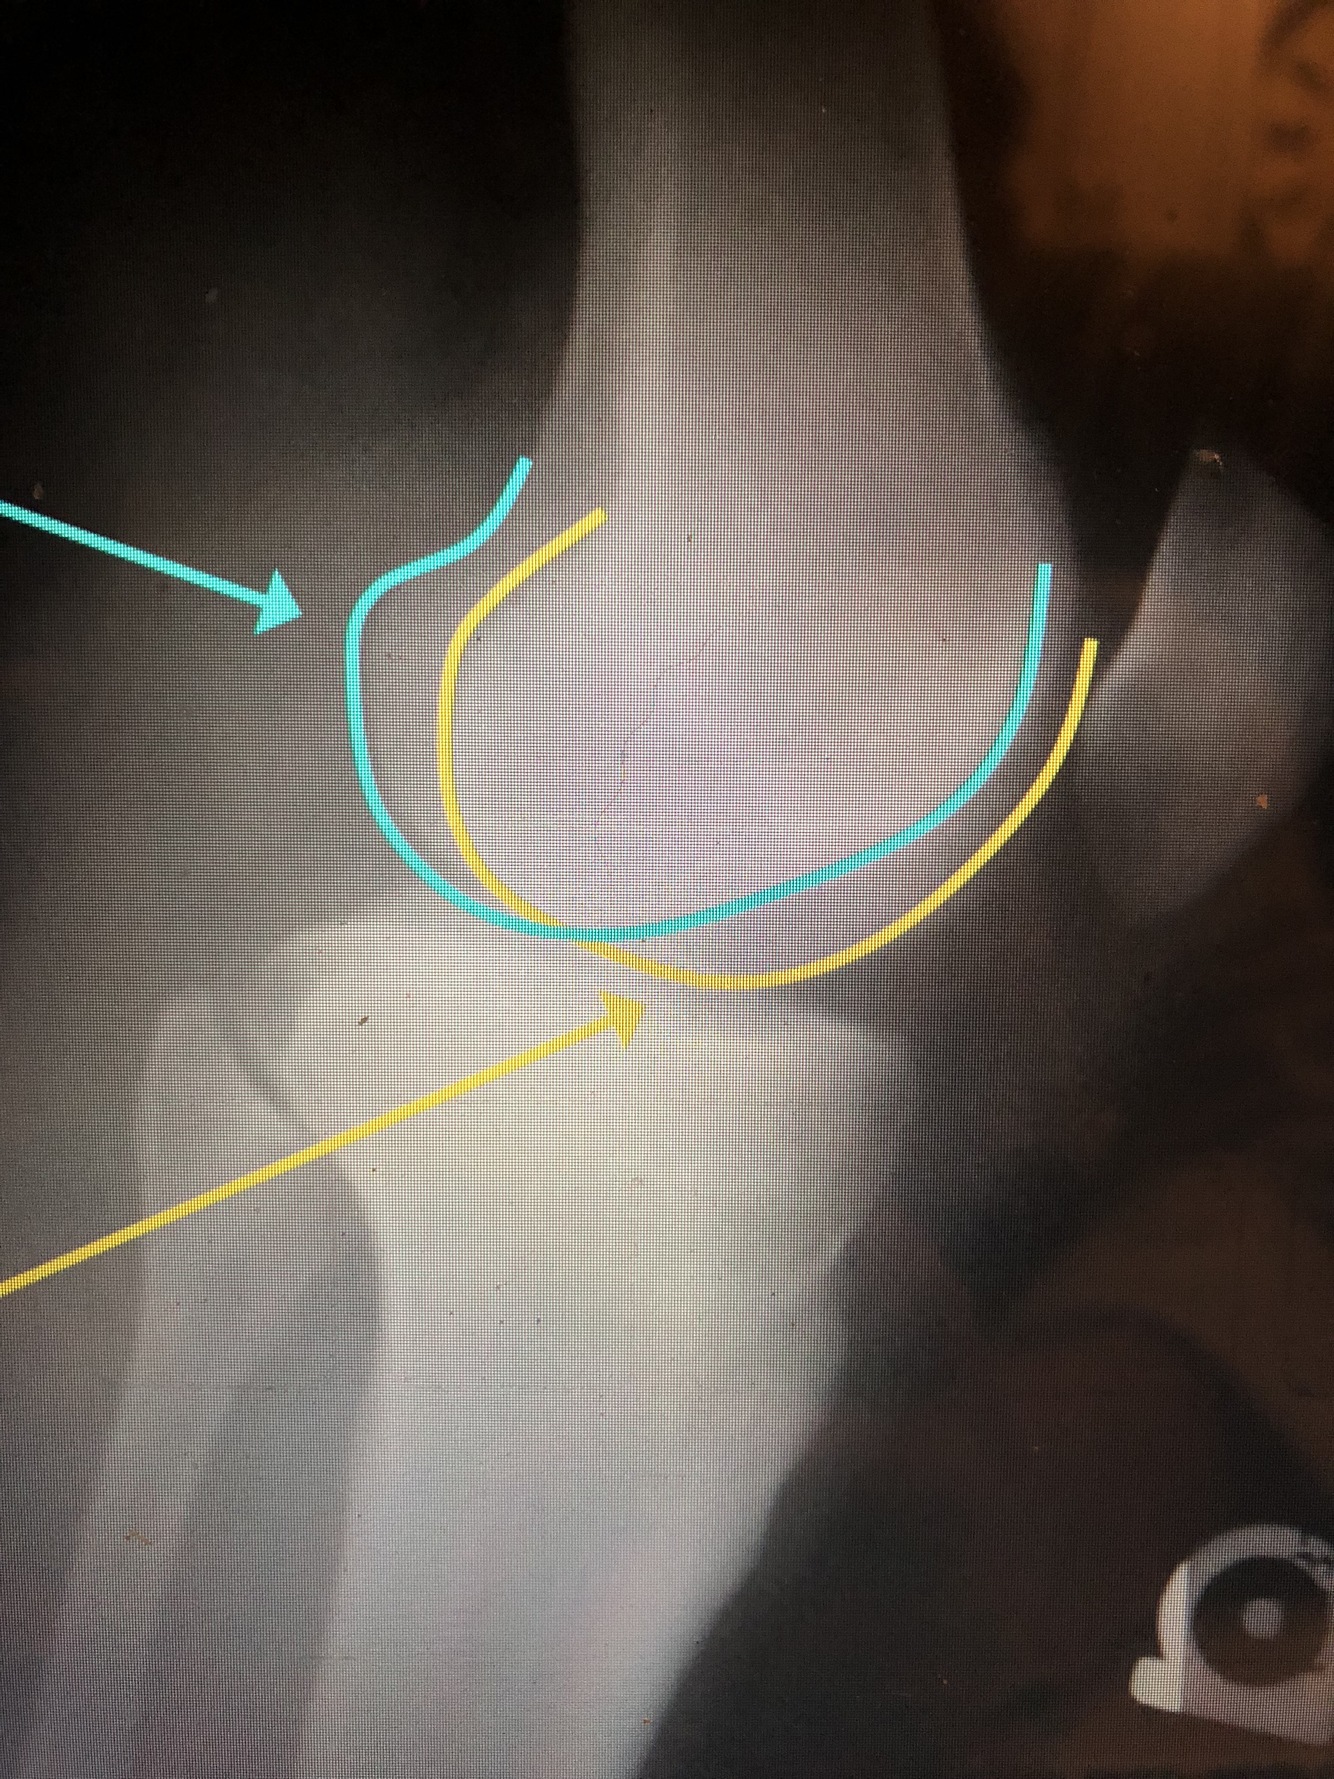

What is the light blue line?

Anterior Margin of the Tibial Condyle

What is the red line?

Tibial Plateau

What is the yellow line?

Posterior Margin of the Tibial Condyle

Styloid Process of the proximal fibula

Articular Facet of the proximal fibula

What is the blue line?

Fibular Head